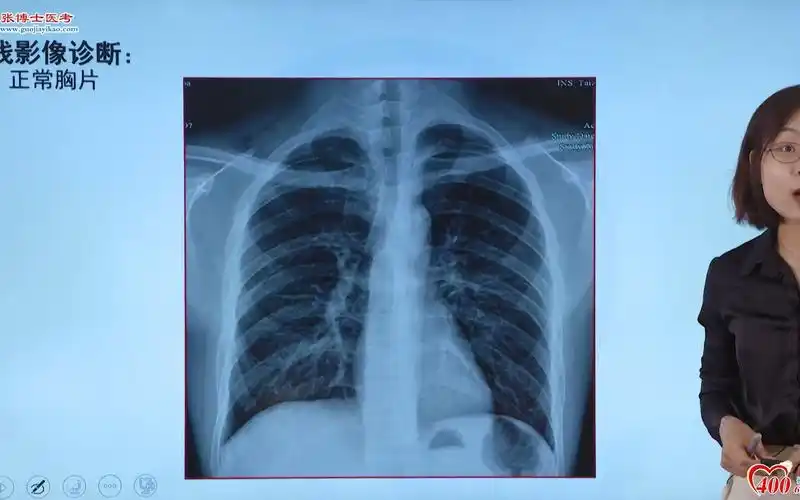

影像-正常胸片